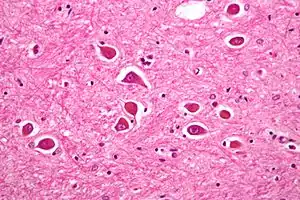

| Micrograph of Alzheimer type II astrocytes, as may be seen in hepatic encephalopathy. | |

There are various explanations why liver dysfunction or portosystemic shunting might lead to encephalopathy. In healthy subjects, nitrogen-containing compounds from the intestine, generated by gut bacteria from food, are transported by the portal vein to the liver, where 80–90% are metabolised through the urea cycle and/or excreted immediately. This process is impaired in all subtypes of hepatic encephalopathy, either because the hepatocytes (liver cells) are incapable of metabolising the waste products or because portal venous blood bypasses the liver through collateral circulation or a medically constructed shunt. Nitrogenous waste products accumulate in the systemic circulation (hence the older term "portosystemic encephalopathy"). The most important waste product is ammonia (NH3). This small molecule crosses the blood–brain barrier and is absorbed and metabolised by the astrocytes, a population of cells in the brain that constitutes 30% of the cerebral cortex. Astrocytes use ammonia when synthesising glutamine from glutamate. The increased levels of glutamine lead to an increase in osmotic pressure in the astrocytes, which become swollen. There is increased activity of the inhibitory γ-aminobutyric acid (GABA) system, and the energy supply to other brain cells is decreased. This can be thought of as an example of brain edema of the "cytotoxic" type.[12]